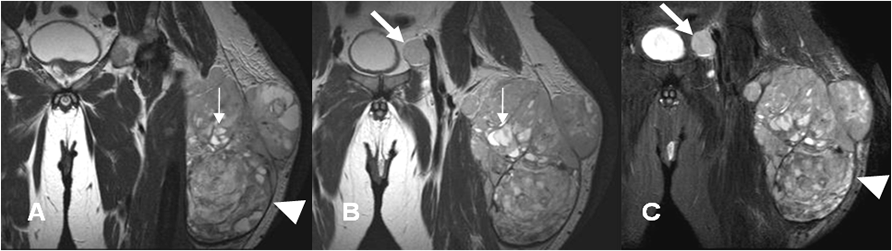

Fig 110 B. Sarcoma pleomórfico indiferenciado.

A y B: RM coronal en T2 y C: RM coronal en STIR. Igual paciente de la Fig 109. Lesión de tejidos blandos, de bordes definidos con una seudocápsula hipointensa (Puntas de flecha) y comportamiento agresivo. Muestra señal heterogénea de predominio hipointenso, con algunas zonas quísticas (Flechas delgadas) y adenopatía metastásica inguinal. (Flecha gruesa).